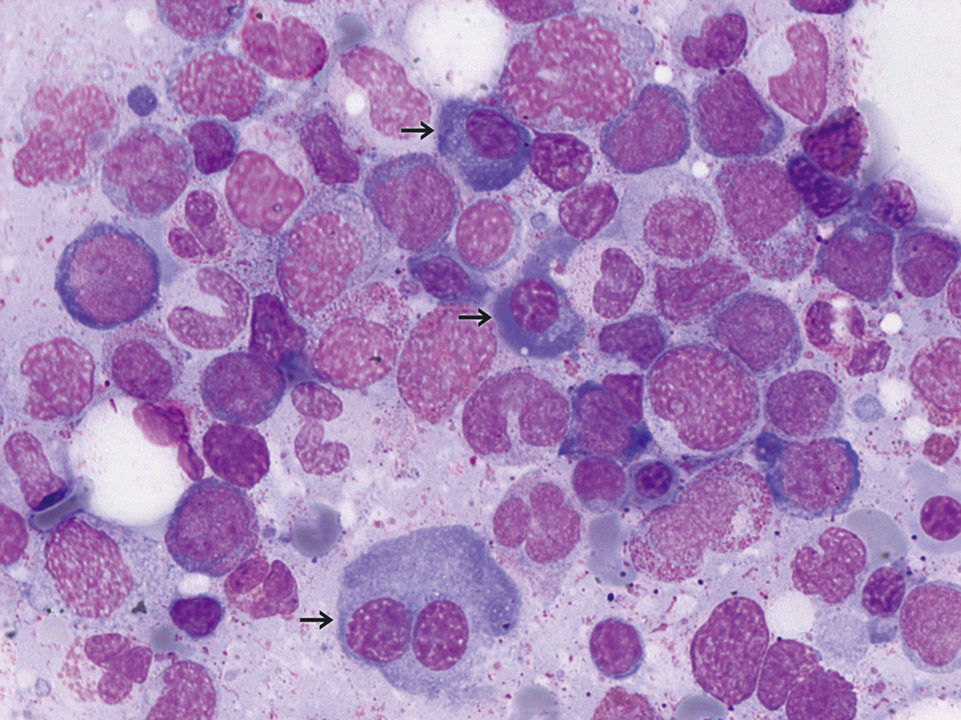

Изучение костного мозга: анатомия и функции